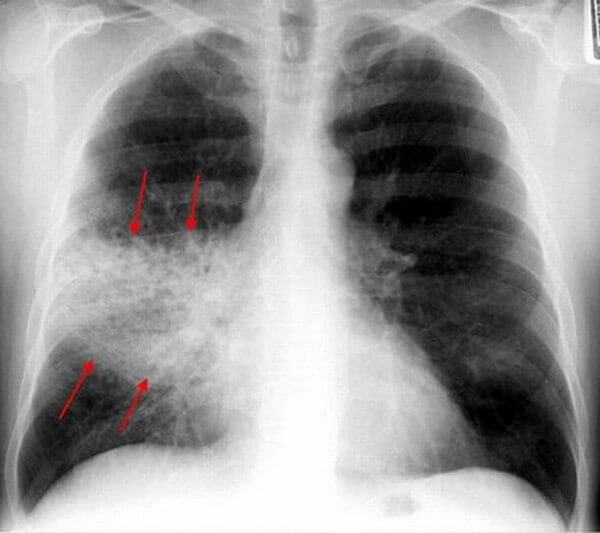

Интерстициальная пневмония – поражения очагового или диффузного характера, протекают с инфильтрацией интерстициальной ткани. У детей данная форма пневмонии вызвана вирусами или пневмоцистами.

На снимке наблюдается увеличение сосудистого пучка и увеличение корней легких. Заметным становится интенсивный силуэт «ветки дерева», что является специфическим признаком болезни.

Фото при интерстициальной пневмонии

- Интерстициальная форма. На снимке заметно уплотнение корней легких и другие изменения, которые формируют выраженный рисунок, напоминающий ветви дерева.